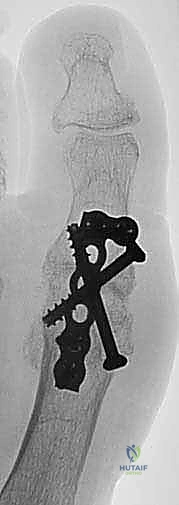

Cannulated or solid screws can be used per the surgeon's preference.23 We use 4.0- or 4.5-mm cannulated screws in most patients. Solid 3.5-mm cortical screws are an alternative (TECH FIG 3B).

- TECH FIG 3 • A. Positioning of the first MTP joint. A flat surface is used to position the toe properly. Note the positioning of the toe to allow for adequate clearance during gait. B. Postoperative radiograph shows the crossed-screw technique.

Our preferred technique also uses a supplementary dorsal plate, which has been shown to provide improved fixation.9,14,21 This is particularly helpful if screws alone provide suboptimal fixation or in patients with osteopenic bone (eg, secondary to rheumatoid arthritis or chronic oral corticosteroid usage).

The plate is then fixed with 2.7-mm nonlocking screws in the phalanx and metatarsal and augmented with 2.7-mm locking screws if bone quality is a concern.8,14 Whether locking or nonlocking screws provide superior fixation remains controversial, with advocates for each (TECH FIG 4).8,13,14,16

- TECH FIG 4 • Dorsal locking plate is used to augment the crossed-screw fixation.